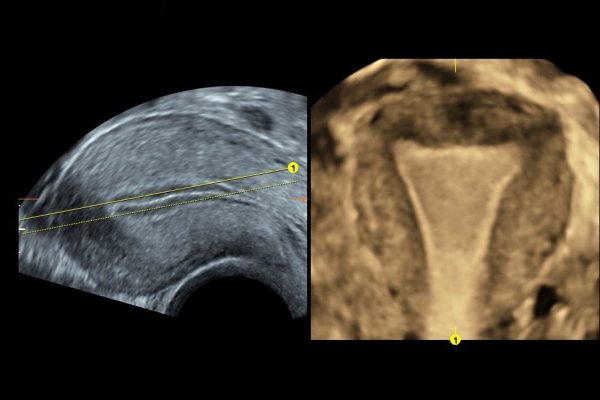

Optimalno je da to bude period između 7. i 10. dana ciklusa. Pretrage započinju uzimanjem uzoraka krvi zbog analiza polnih hormona i hormona štitne žlijezde. Nakon uzimanja uzorka krvi radi se 3D ultrazvučni pregled materične šupljine sa ciljem provjere građe materične šupljine, 3D pregled jajnika sa ciljem procjene “rezerve jajnika”, potom se provodi procedura testiranja prohodnosti jajovoda također pod kontrolom 3D ultrazvuka. Istovremeno mušarac daje uzorak sjemena za analizu (potrebno je 3.-5. dana apstinencije)

- 3D pregled građe materične šupljine

- 3D sono HSG (test prohodnosti jajovoda sa trodimenzonalnim prikazom)